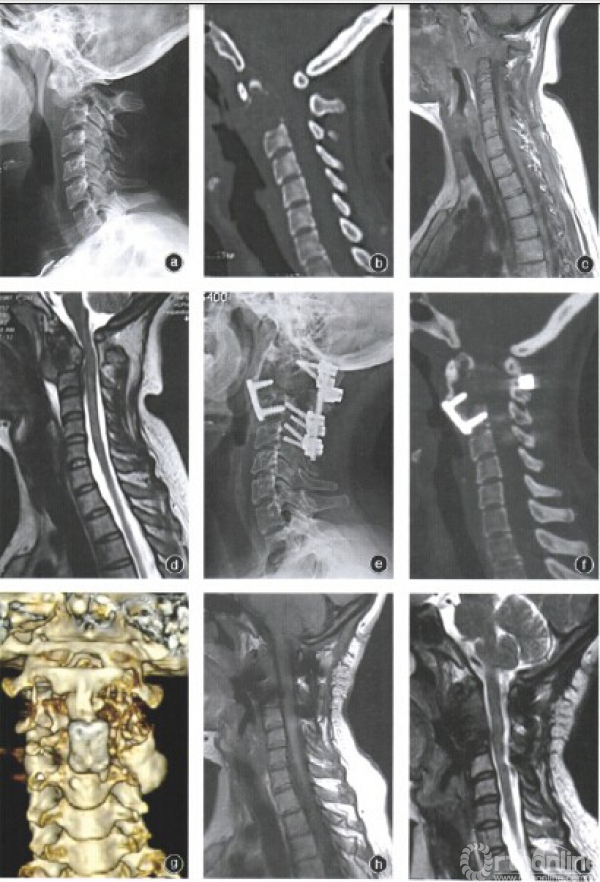

5例患者均采用全身麻醉,并在全麻下进行动脉血压监测和留置深静脉插管,以便于大出血时及时补充血容量。5例患者均采用前后路联合人路保留齿突的手术方案。后路采用跨C2的椎弓根钉一棒系统固定寰椎椎弓根及C3侧块,其中2例齿突合并病理性骨折者后路固定寰椎椎弓根及C3,C4侧块,以稳定颈椎。前路采用胸锁乳突肌内缘下颌角人路显露病椎(图1a),对病椎骨壳相对完整者,行骨壳内病灶刮除(图1b),注意刮除齿突内肿瘤,肿瘤刮除后,用质量浓度50%的氯化锌烧灼瘤腔,反复冲洗后植入B—TCP人工骨颗粒;对病椎骨皮质被破坏者,行椎体肿瘤分块切除,保留齿突,齿突内肿瘤给予刮除,取自体髂骨块,将髂骨块修整为大致“菜刀形”,刀柄插入齿突,刀体植于病椎切除后的骨缺损处,与齿突及C3,椎体融合,应用前路钢板内固定(图1c)。1例复发病例由于肿瘤沿椎弓根向前方椎体侵袭破坏,MRI提示有液平面现象,主要为动脉瘤样骨囊肿成分,故单纯从后路由两侧椎弓根进入,向前刮除椎体及齿状突内肿瘤,植入B-TCP人工骨颗粒重建。

三、重建效果

3例骨包壳完整植入,B-TCP人工骨颗粒的患者,术后第3个月可见植骨颗粒边界和内部结构模糊,术后12个月可见植骨中心区域植骨颗粒融合成片。随着时间推移,植骨颗粒的成骨降解均满意,形成自身骨质(图2)。2例取髂骨结构性植骨的患者,术后6个月可见植骨块与齿突、C,椎体融合,术后12个月达到完全愈合(图3)。生物学重建植骨均达到理想的效果(图4)。

四、临床功能及影像学评估

术后3个月随访,5例患者颈枕屈伸功能基本正常,颈椎旋转度大约为正常颈椎旋转度的60%。随访期间的影像学检查,x线片示颈椎稳定性满意,三维CT及MRI提示未见肿瘤复发,植骨愈合满意,椎管通畅,未见占位性受压。未见内置物失败病例。